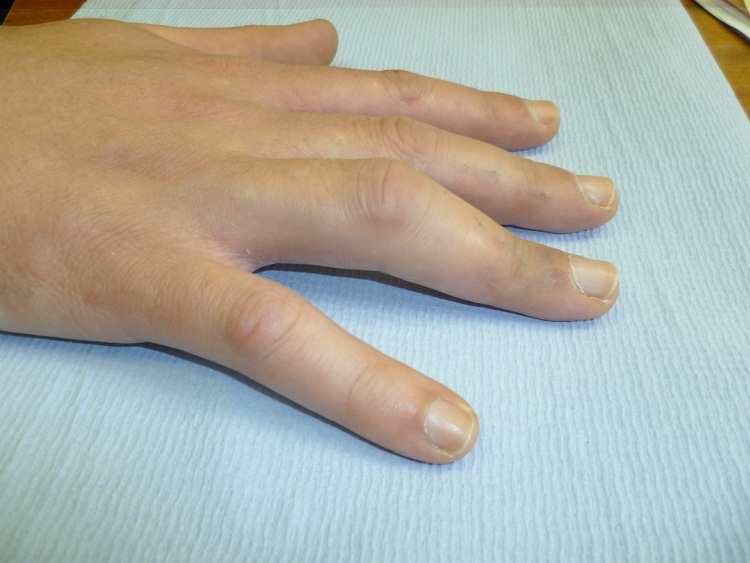

A 56-year-old fit and well man presented to the hand trauma clinic with a one week history of pain and swelling to his right ring finger. He recalls lifting a garden pot and feeling a sudden pain in his finger.

A photograph of his hand is shown below; radiographs were normal.

What is the deformity and what is the diagnosis?

Boutonniere deformity due to central slip rupture